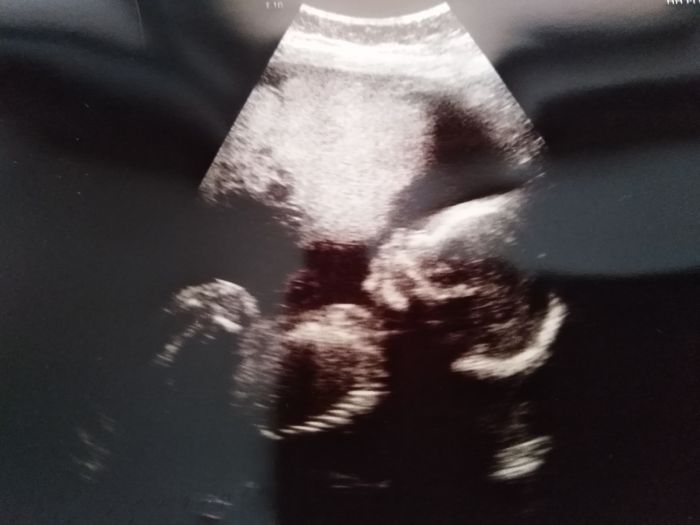

Ahoj holky, ve čtvrtek na kontrole dopadlo vše dobře. Vzhledem k předchozímu potratu kvůli vade kosti, sem byla u doktorky dlouho. Na ultrazvuku se koukala jestli má malej všechny kosti jak mají být. A vše dopadlo dobře ?. Malej se nechtěl otočit tak sem asi 20min. chodila po ordinaci ?. Na cukrovku jdu od 29.1. Takže se objednám až na únor. Mám aji fotku